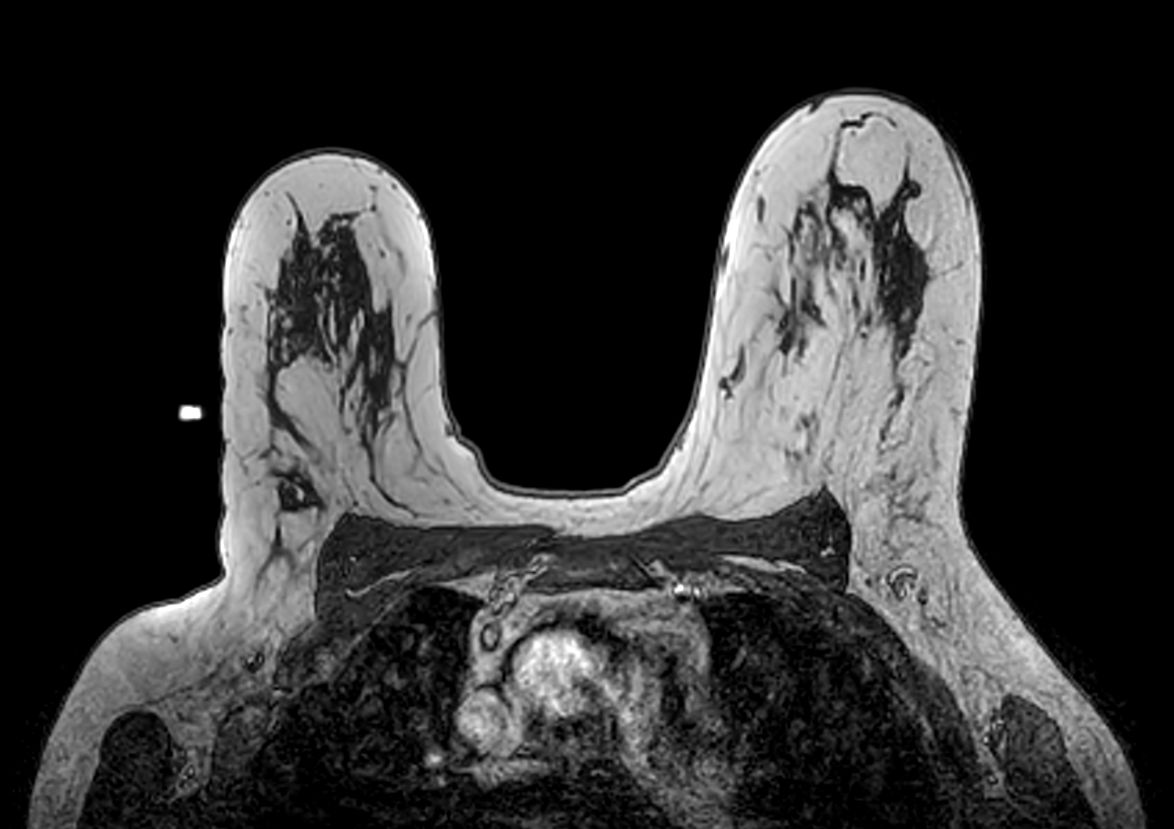

Axial 3D T1w FFE Post-biopsy check, clip inserted